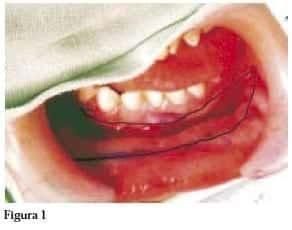

Previa demarcación e infiltración de la mucosa oral con una solución de lidocaina al 1% con epinefrina 1:100.000, se toma con bisturí el injerto, (hay que calcular un 20% más en el tamaño, debido a la retracción), en este caso de la cara interna del labio inferior. El defecto oral se cerró con ácido poliglicólico 4-0.

(figura 1)